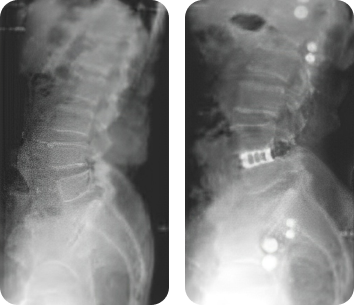

Клинический пример

Применение кейджей VariAn ExpandableTM при хирургическом лечении спондилолистеза и сколиотической деформации.

- Пациент:

- Женщина, 51 год.

- Диагноз:

- Дегенеративный спондилолистез поясничного отдела позвоночника со стенозом позвоночного канала.

- Лечение:

- Выполнена редукция и фиксация кейдами VariAn ExpandableTM. Контрольные рентгенограммы выполнены через 1 и 2 года после операции.